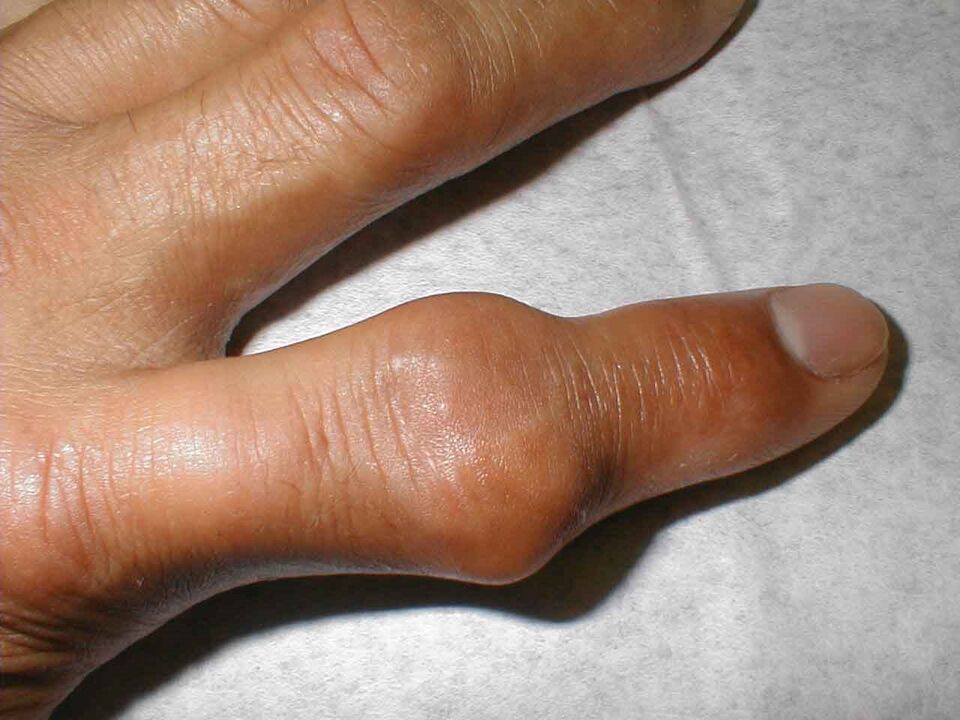

Os dedos incham e doem mesmo em repouso. A dor geralmente ocorre à noite. O início da doença pode ser agudo, observa-se vermelhidão nas articulações falangeanas, são quentes e densas ao toque. A temperatura de todo o corpo pode aumentar.

Artrite ou inflamação das articulações dos dedos pode ocorrer devido à penetração da flora bacteriana neles. Na maioria das vezes, são estafilococos ou estreptococos. A bactéria causa inflamação aguda, caracterizada por forte inchaço das articulações, vermelhidão e aumento da temperatura local.

A síndrome da dor é pronunciada. O paciente queixa-se de espasmos e dores agudas, mesmo em repouso. É quase impossível apertar as mãos; tentar tomar qualquer coisa é acompanhado por fortes sensações dolorosas.

A articulação aumenta de tamanho e fica vermelha. É impossível tocá-lo e os analgésicos pouco ajudam. Essa síndrome de dor intensa é causada pelo acúmulo de cristais pontiagudos de sais (uratos) na cavidade articular, que penetram nos tecidos moles a cada movimento, ferindo-os.

A ligamentite estenosante começa a progredir como resultado da inflamação do ligamento localizado na base do dedo indicador. À medida que a doença progride, surge o “estalo” do dedo, quando a flexão é dolorosa e difícil, e a extensão sem a ajuda da segunda mão torna-se quase impossível. Na base, no lugar do ligamento inflamado, é palpada uma densa formação redonda. Nesse caso, a dor pode se espalhar por toda a mão e irradiar para o pescoço. Externamente, os dedos parecem azulados e inchados.